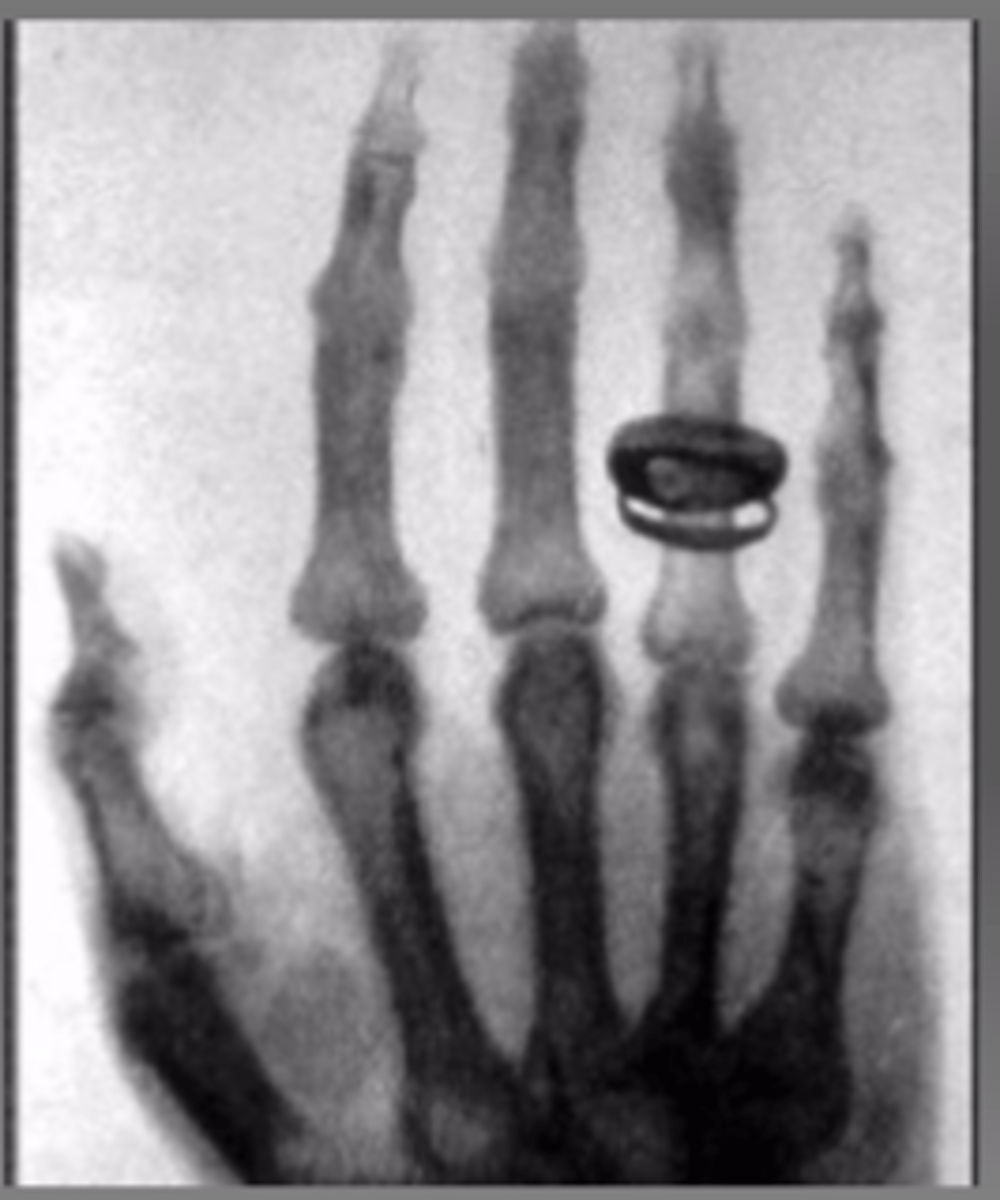

First human radiograph

of Roentgen's wife!